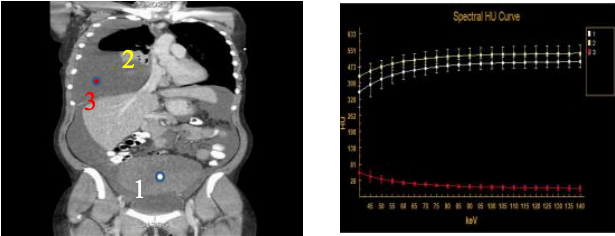

能谱功能分析

肾输尿管膀胱结石

不同的结石成分,可以采用不同的治疗方法。传统治疗方法是在没有取出结石以前是没有办法鉴定结石的成分的,不知道具体的治疗方案,有了能谱就可以在没有取出结石之前就可以知道结石的成分了。 知道了成分,就可以给临床医生治疗提供最适合的治疗方案

肿瘤的同源性鉴别

如果发现一个人体内两个不同器官上分别发现两个肿瘤,我们首先需要区分的是这两个肿瘤到底是其中一个转移给另一个的(同源性转移瘤)。还是这两个器官分别长的不同肿瘤(原发瘤), 能谱扫描可以发现两个不同器官上的两个不同的肿瘤成分是否一致

痛风检查

能谱扫描可以及时发现尿酸结石附着。 能谱分析可以确定痛风结节成分,可以指导临床采用保守治疗还是手术治疗。

整机标配能谱功能

物质分离与成分分析

能谱CT可区分组织中的水、碘、钙、尿酸盐等不同成分。例如,在痛风患者中,能将尿酸盐结晶特异性标记为绿色,钙化灶标为紫色,实现分子级显影,有助于早期发现和疗效监

单能量成像:优化图像质量

可生成40–140 keV范围内的虚拟单能量图像。低能量(如40–70 keV)可增强对比度,利于小病灶检出;高能量(如100–140 keV)则可有效去除金属伪影,提升图像清晰度

能谱曲线分析:辅助良恶性鉴别

每种组织都有独特的“能谱指纹”。通过分析病灶在不同能量下的CT值变化曲线,可辅助判断肿瘤来源、良恶性及分级。例如,恶性肿瘤常表现为陡峭的能谱曲线,而良性病灶则趋于平缓